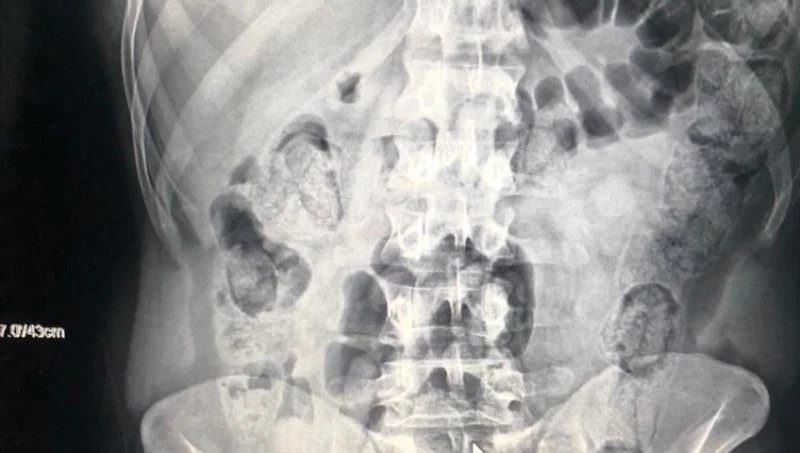

Edinilen bilgiye göre, Kocaeli TEM Otoyolu’nda bir yolcu otobüsünü durdurarak arama yapan Narkotik polisleri, hareketlerinden şüphelendikleri İran uyruklu şahsın bagajlarında yaptıkları aramalarda üzerinde dışkı kalıntısı olan prezervatiflere sarılı 25 paket metamfetamin adlı uyuşturucu maddesi ele geçirdi. Uyuşturucuları yuttukları şüphesiyle hastaneye götürülen şahısların çekilen röntgenlerinde, midelerinde kapsüller halinde uyuşturucu olduğu belirlendi.

Tespit sonrasında şahısların midelerinden hekim kontrolünde 103 paket halinde 871 gram metamfetamin maddesi çıkartıldı. Emniyet Müdürlüğüne götürülen 3 şahsın, tamamlanan işlemleri sonrasında adliyeye sevk edilmesi bekleniyor.